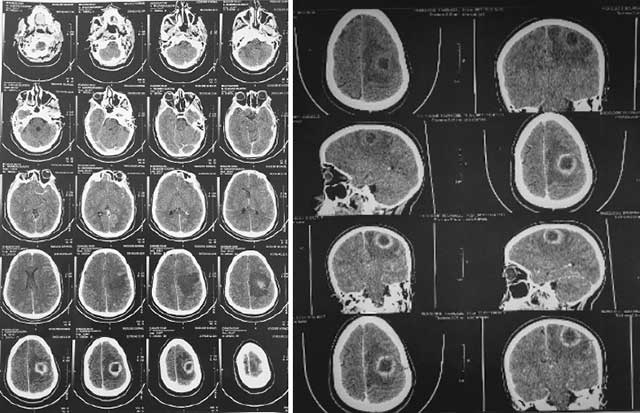

Une TDM cérébrale sans et avec injection de produit de contraste a été prescrite, et dont le résultat était en faveur d’un processus occupant l’espace pariétal gauche (Fig. 1 et 2) dont les caractéristiques et le comportement après injection de produit de contraste évoquent en premier une origine tumorale ou infectieuse probable.

L’examen anatomopathologique objective un aspect histologique d’une encéphalite abcédée sans caractère inflammatoire spécifique (Fig. 3).

Examen cytobactériologique : Présence de Fusobacterium à Gram négatif et forte suspicion d’anaérobie (Fig. 4).